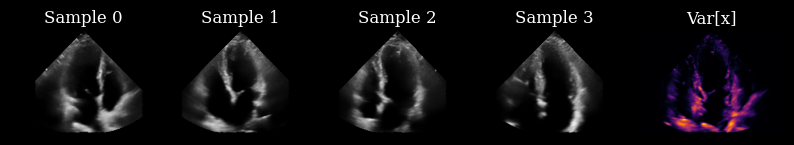

Initially, we have not yet acquired any measurements, so we draw samples from the prior to drive our actions.

[9]:

prior_samples = model.sample(n_samples=n_prior_samples, n_steps=n_unconditional_steps, verbose=True)

scan_converted_prior_samples = scan_convert(

data=keras.ops.squeeze(prior_samples, axis=-1), **parameters

)["data"]

posterior_variance = ops.nan_to_num(ops.var(scan_converted_prior_samples, axis=0))

fig, _ = plot_image_grid(

list(scan_converted_prior_samples) + [translate(posterior_variance, range_to=(-1, 1))],

titles=[f"Sample {i}" for i in range(n_prior_samples)] + ["Var[x]"],

vmin=-1,

vmax=1,

cmap=["gray"] * n_prior_samples + ["inferno"],

)

90/90 ━━━━━━━━━━━━━━━━━━━━ 12s 46ms/step

../../_images/notebooks_agent_agent_example_17_1.png